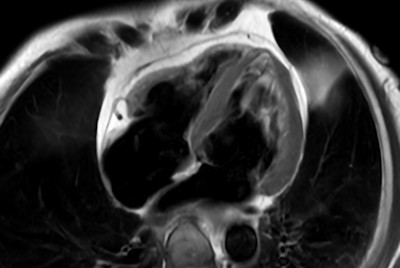

Comprehensive Cardiac with SmartSpeed Precise

Myocardial infarction with T1/T2 Mapping

Cardiac infarction with Compressed SENSE

Cardiac infarction with fat-free mDIXON imaging

Cardiac imaging with Compressed SENSE

Acute myocardial infarction

30 minute Cardiac Function and Fibrosis at 1.5T

30 minute Cardiac Function and Fibrosis at 3.0T

Cardiac MRI - Arrhythmia patient

Cardiac MRI at 3.0T